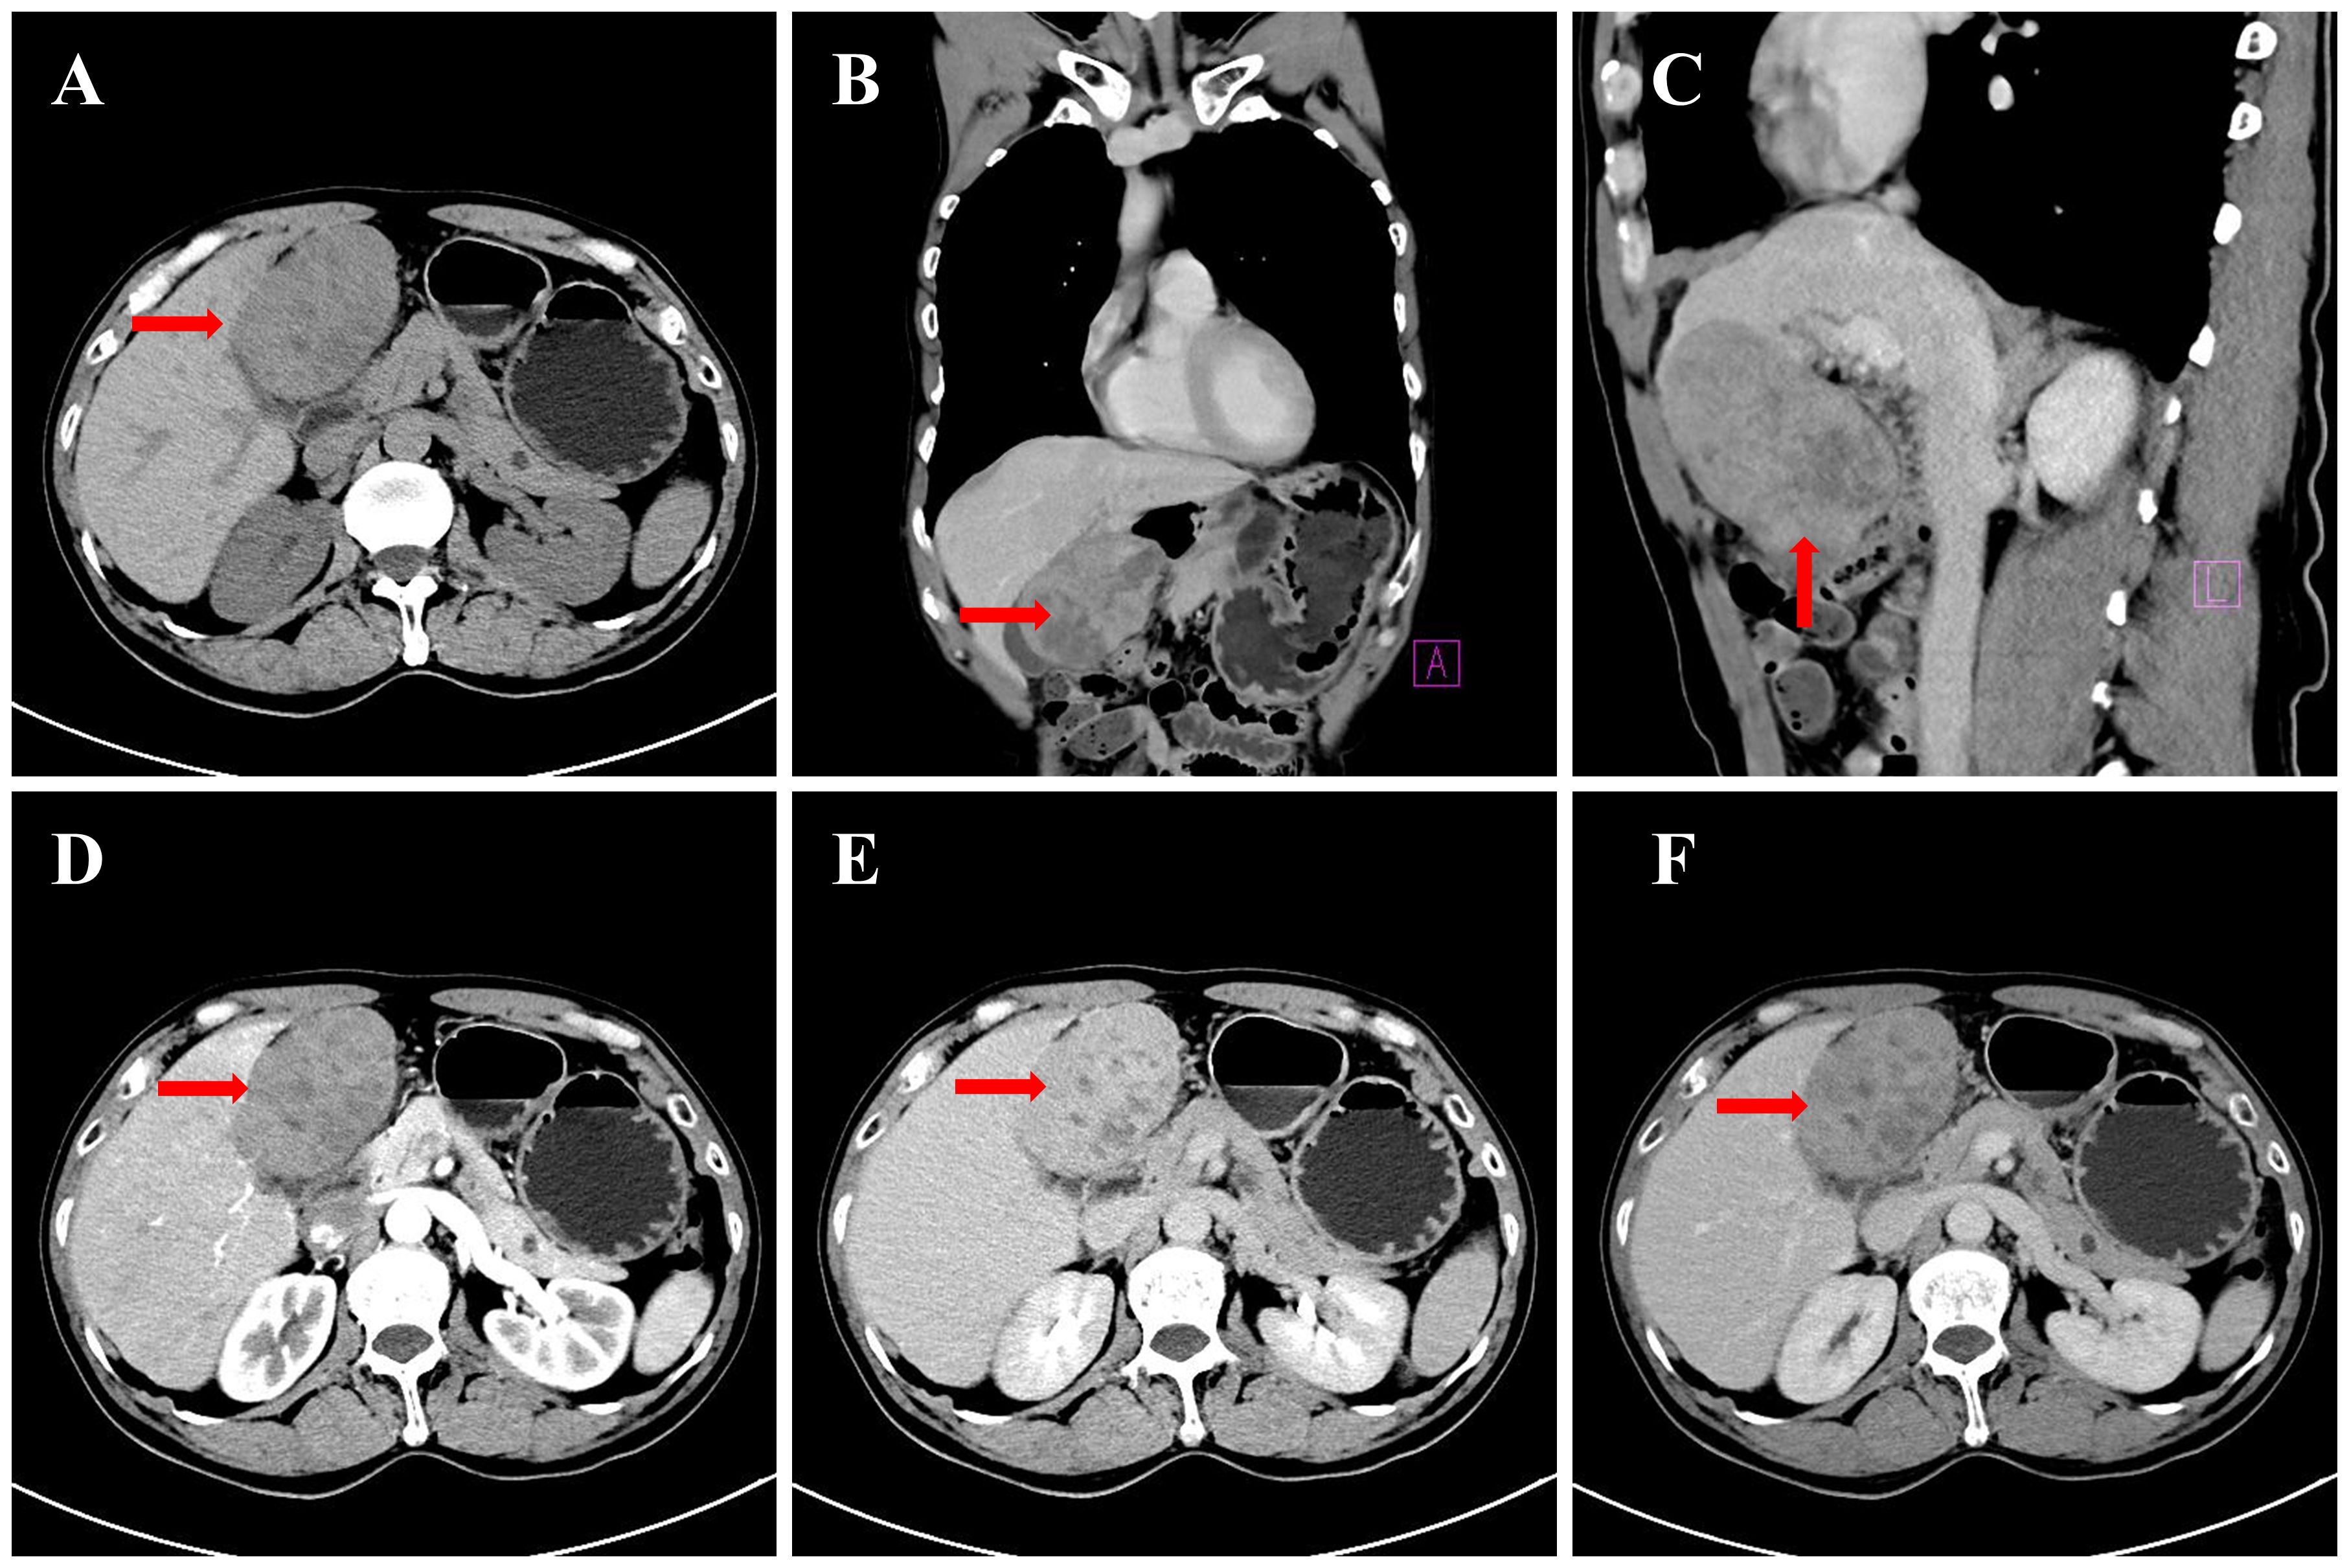

Background: Primary hepatic leiomyosarcoma (PHL) is an extremely rare malignancy often misdiagnosed due to nonspecific imaging features overlapping with cholangiocarcinoma. This case highlights diagnostic challenges and the potential association of SDHB positivity with PHL prognosis. Case Presentation: A middle-aged male presented with an asymptomatic liver mass. Preoperative CT/MRI revealed a 10-cm lesion with progressive heterogeneous enhancement and delayed capsular enhancement, initially diagnosed as cholangiocarcinoma. Left hepatic lobectomy confirmed PHL. Immunohistochemistry showed SDHB positivity and low Ki67 (15%). The patient recovered well with no recurrence at 6-month follow-up. Conclusions: PHL can radiologically mimic cholangiocarcinoma, necessitating inclusion in differential diagnoses for "cholangiocarcinoma-like" liver masses. SDHB positivity may indicate favorable tumor biology, but further studies are needed to validate its prognostic value. Surgical resection remains curative for localized PHL.